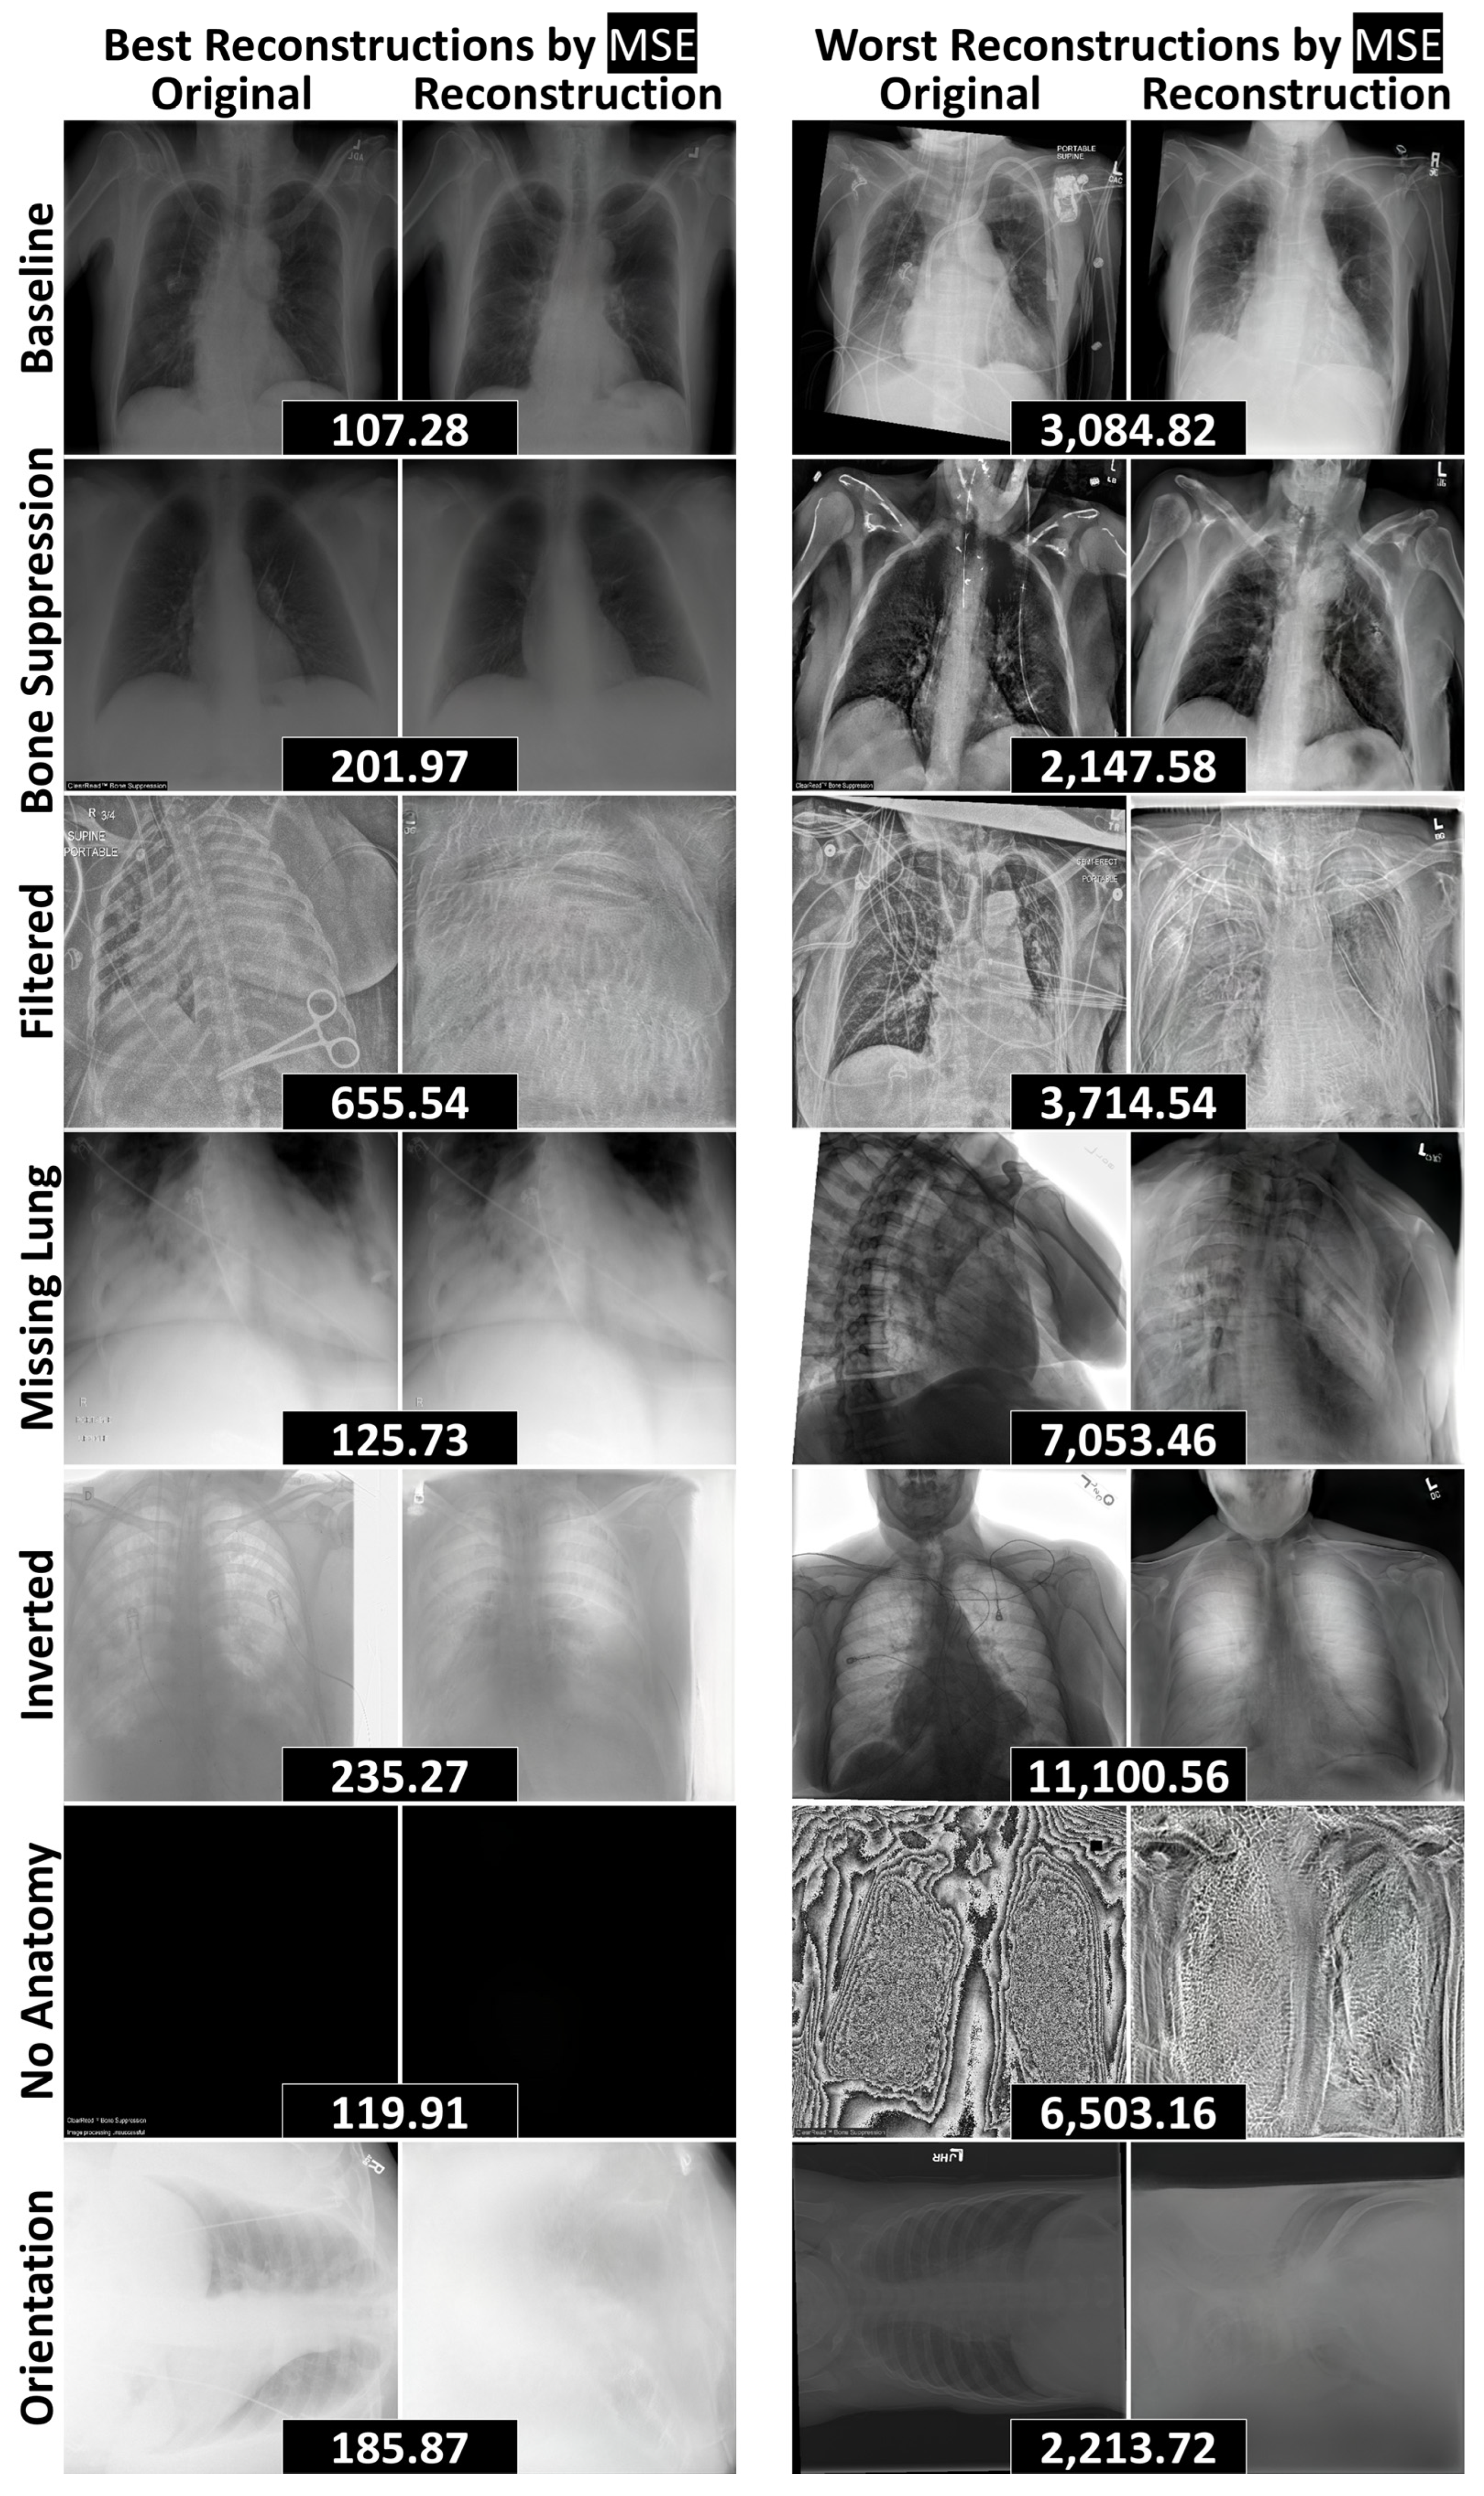

3.2. Reconstruction Performance and Interpretation